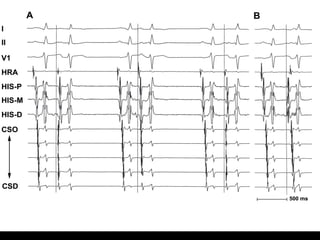

Intracardiac EKG

If the earliest signal is recorded by   The origin of the AT is most likely

the…                                    the…

HIS EGM                                 Anteroseptal RA

Proximal CS EGM                         Posteroseptal RA

Low or high RA EGM                      Somewhere in the RA

Distal CS EGM                           Lateral LA

HRA EGM                                 Right superior pulmonary vein